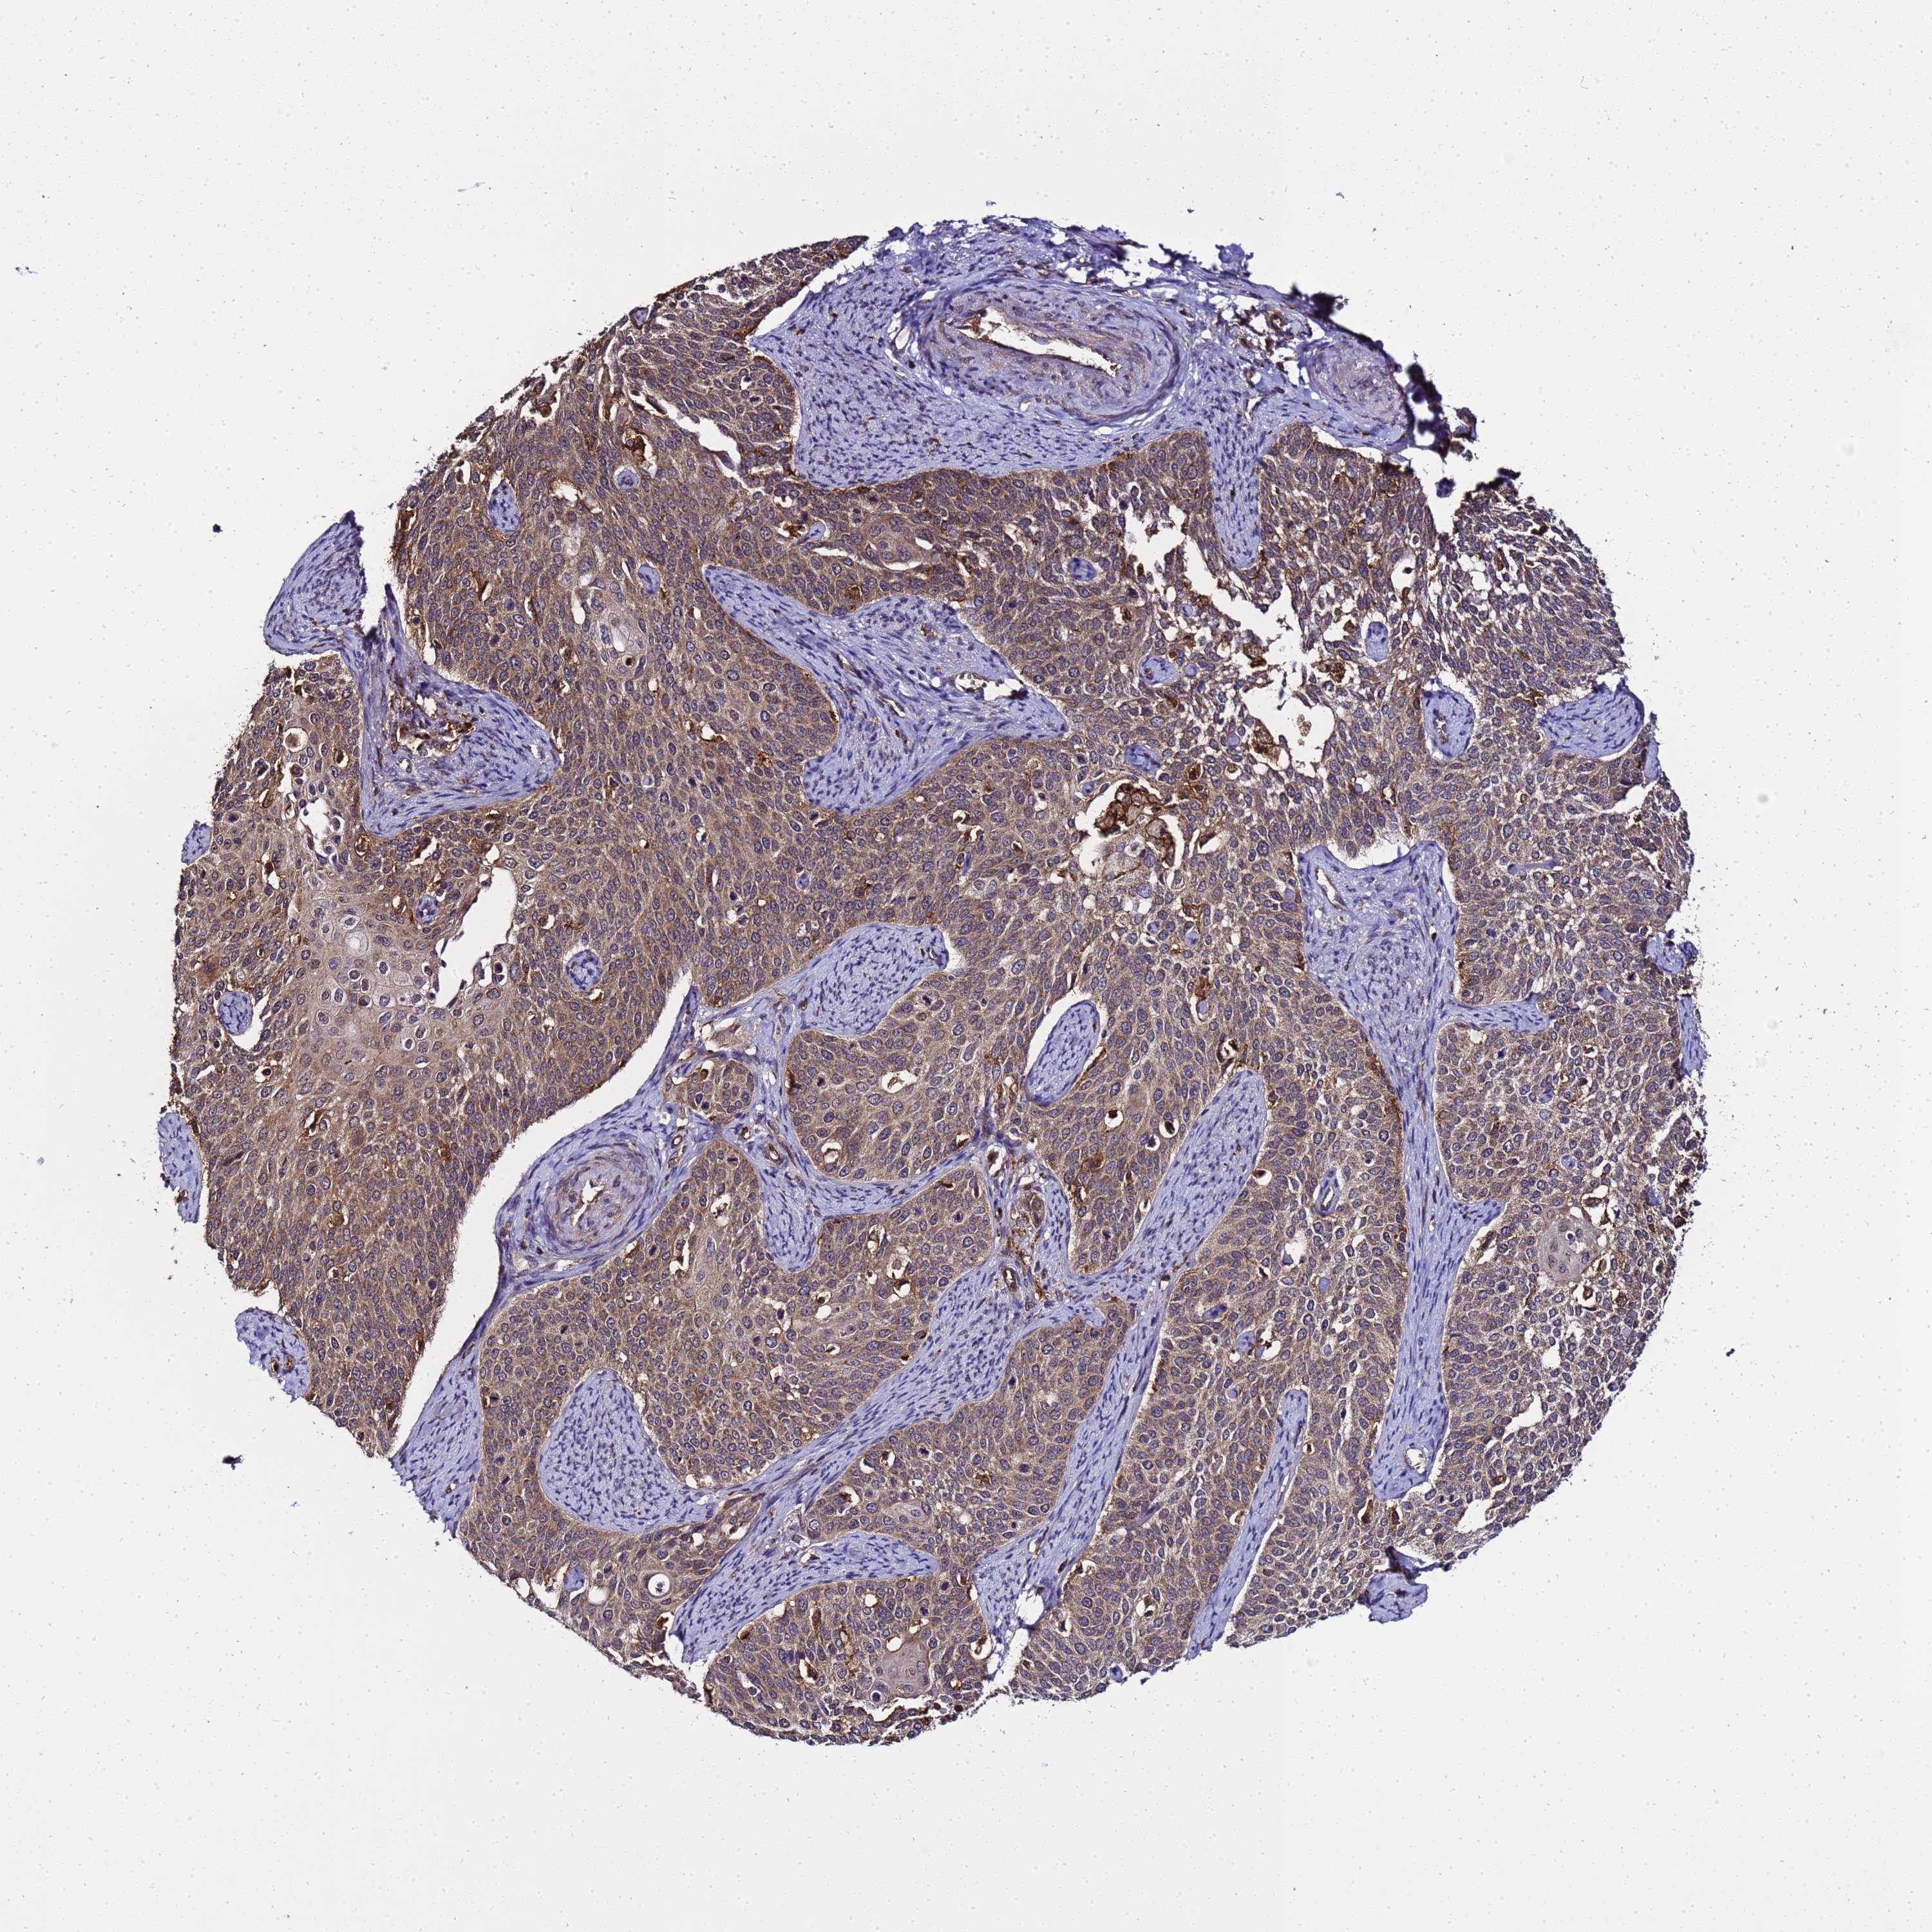

CERVICAL CANCER - Protein expressioni

A mouse-over function shows sample information and annotation data. Click on an image to view it in a full screen mode. Samples can be filtered based on level of antibody staining by selecting one or several of the following categories: high, medium, low and not detected. The assay and annotation is described here.

Note that samples used for immunohistochemistry by the Human Protein Atlas do not correspond to samples in the TCGA dataset.

Antibody stainingi

Antibody staining in the annotated cell types in the current human tissue is reported as not detected, low, medium, or high, based on conventional immunohistochemistry profiling in selected tissues. This score is based on the combination of the staining intensity and fraction of stained cells.

Each image is clickable and will lead to virtual microscopy that enables deeper exploration of all samples and also displays staining intensity scores, fraction scores and subcellular localization as well as patient and tissue information for each sample.

Antibody HPA000822

Staining

High

Medium

Low

Not detected

Intensity

Strong

Moderate

Weak

Negative

Quantity

>75%

75%-25%

<25%

None

Location

Nuclear

Cytoplasmic/membranous

Cytoplasmic/membranous,nuclear

Squamous cell carcinoma, NOS

Adenocarcinoma, NOS